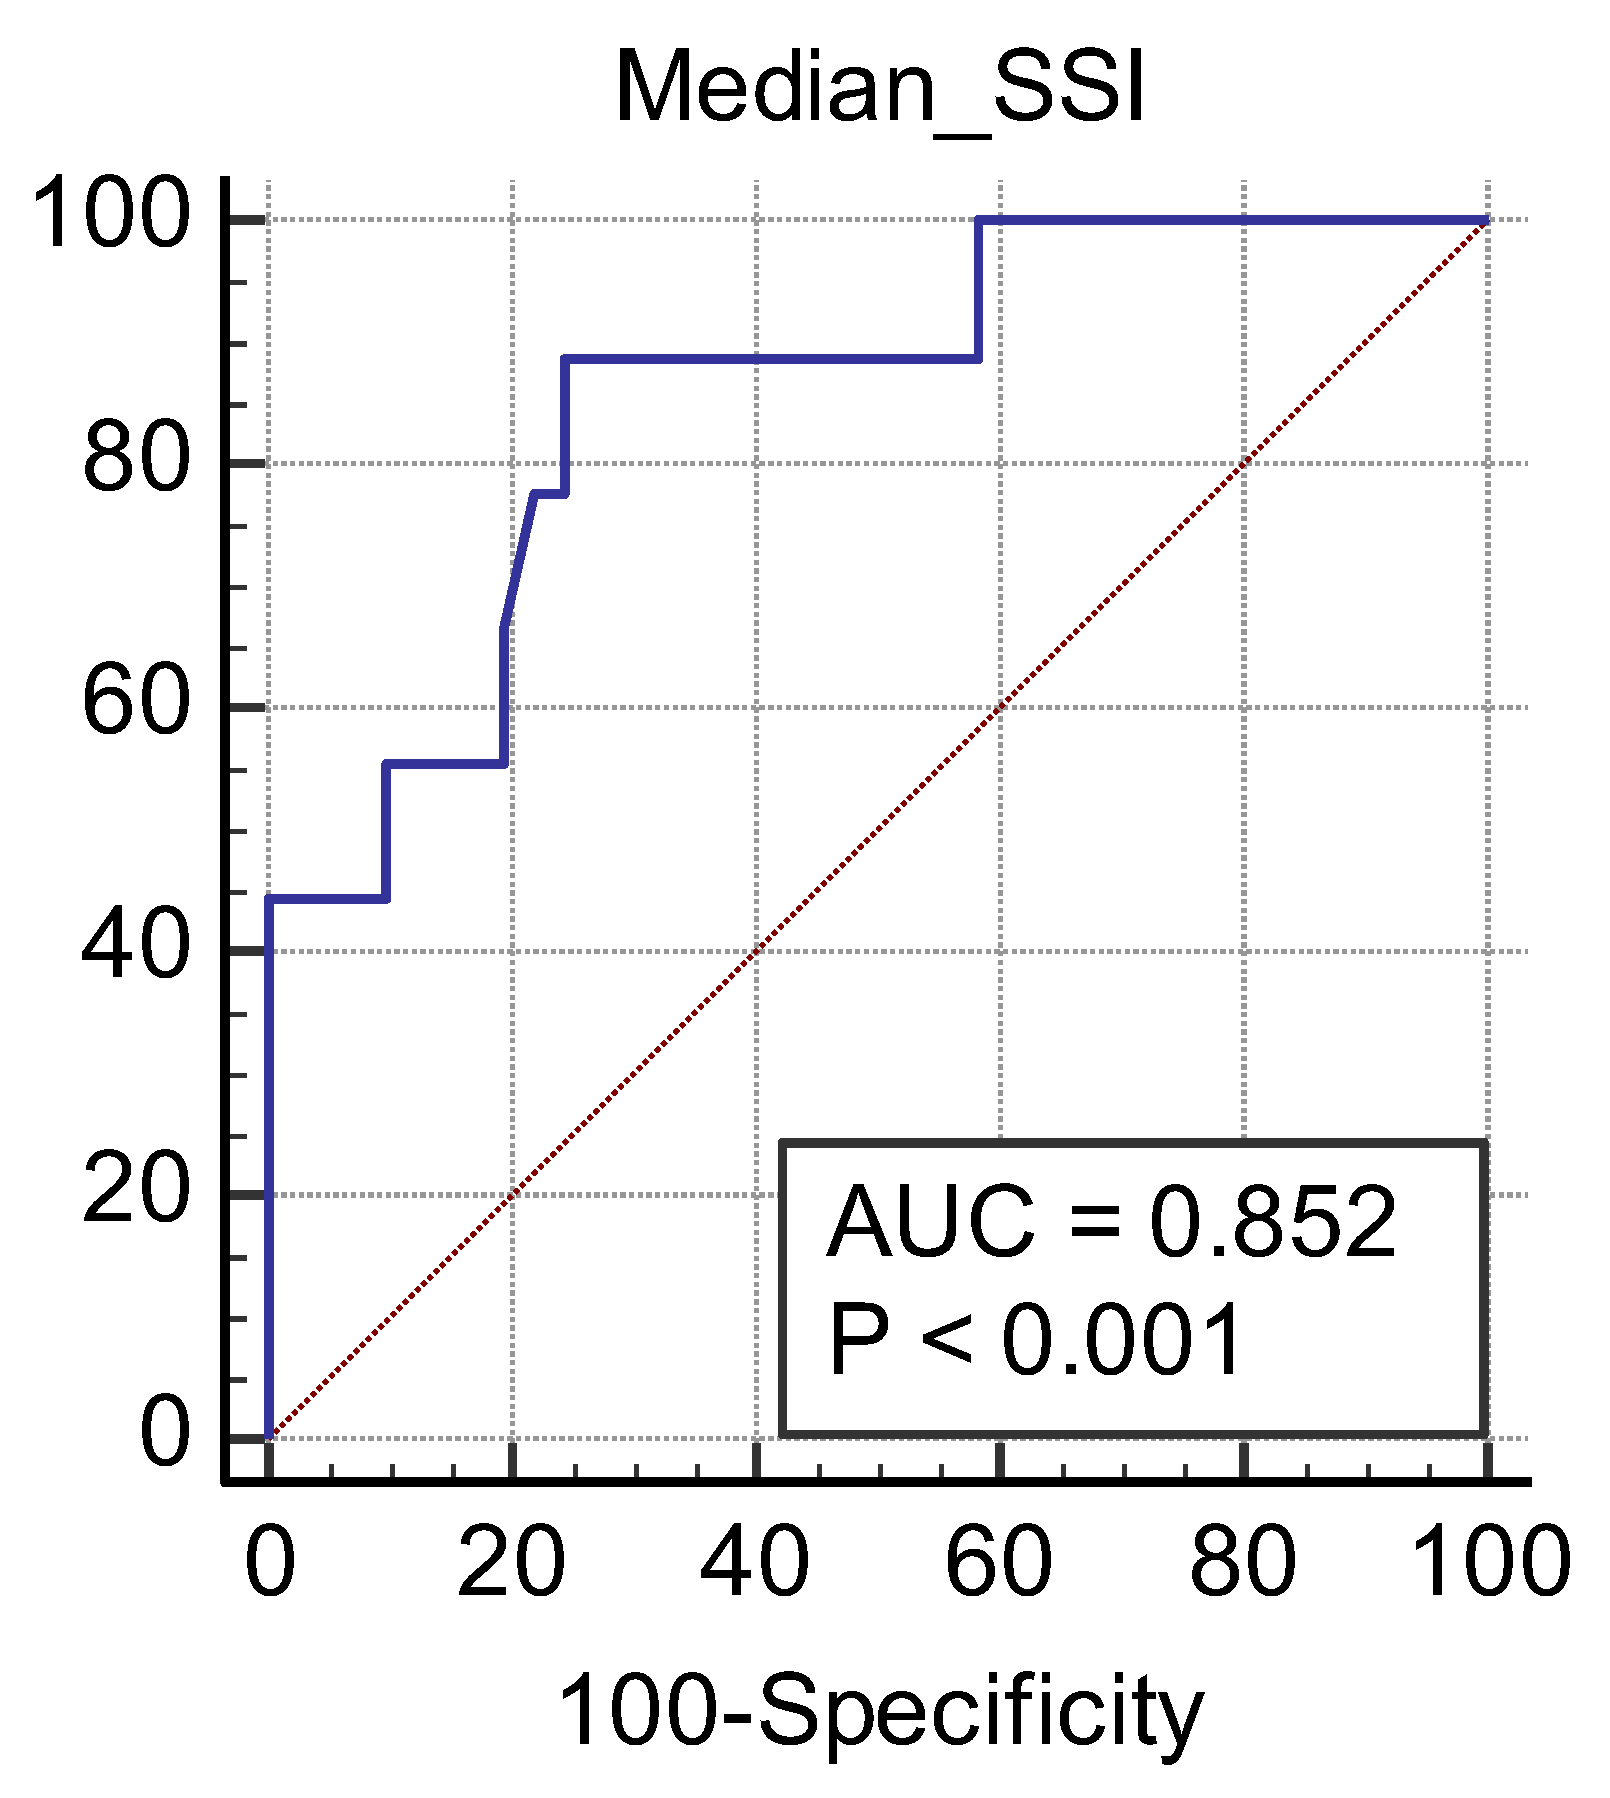

3. Results